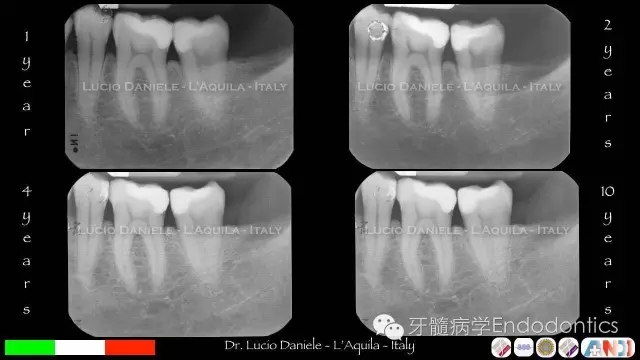

圖16.隨訪1年、2年、4年、10年

圖28.臨床研究:MTA用于成直接蓋髓的效果。MTA直接蓋髓的10年成功率達(dá)92.5%。80顆活髓牙中,只有6顆牙齒需要根管治療,其他74顆牙齒仍是活髓,牙髓未鈣化,無(wú)牙根吸收。